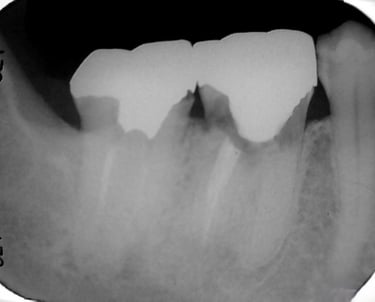

Se identifica si hay fracturas en la raíz del diente, que pueden causar dolor, infecciones o problemas de estabilidad dental. Se utilizan radiografías y exámenes clínicos para este diagnóstico.

Evaluación de fracturas radiculares